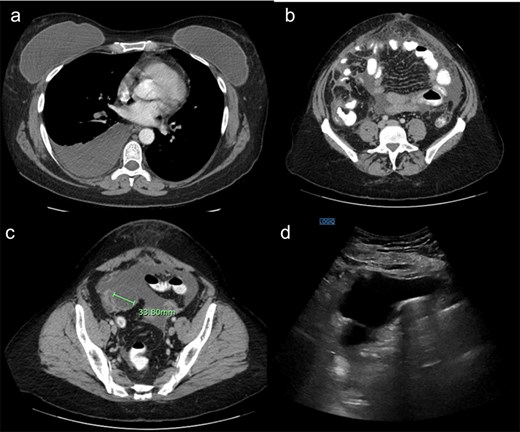

Laboratory testing revealed leukocytosis (WBC 11.7 × 109/L) and elevated CA-125 (516 U/mL). Contrast-enhanced computed tomagraphy (CT) demonstrated moderate ascites, omental caking, nodular peritoneal thickening, a small adnexal mass, and bilateral pleural effusions, (Fig. 1). These features were concerning for an advanced gynecologic malignancy. Diagnostic paracentesis and thoracentesis were non-diagnostic: cytology was negative for malignant cells and no organisms were identified on routine stains or cultures. Given that there was persistent concern for carcinomatosis, she underwent diagnostic laparoscopy. Intraoperatively there was diffuse peritoneal studding and straw-colored ascites. Biopsies revealed necrotizing granulomatous inflammation containing thick-walled spherules consistent with Coccidioides with fungal cultures subsequently confirming the diagnosis (Fig. 2).

(a) Demonstrating right pleural effusion, likely from pulmonary coccidioidomycosis. (b) Demonstrating thickened anterior omental fat concerning for peritoneal carcinomatosis. (c) Demonstrating a right adnexal mass. (d) Ultrasound demonstrating a large amount of ascites.